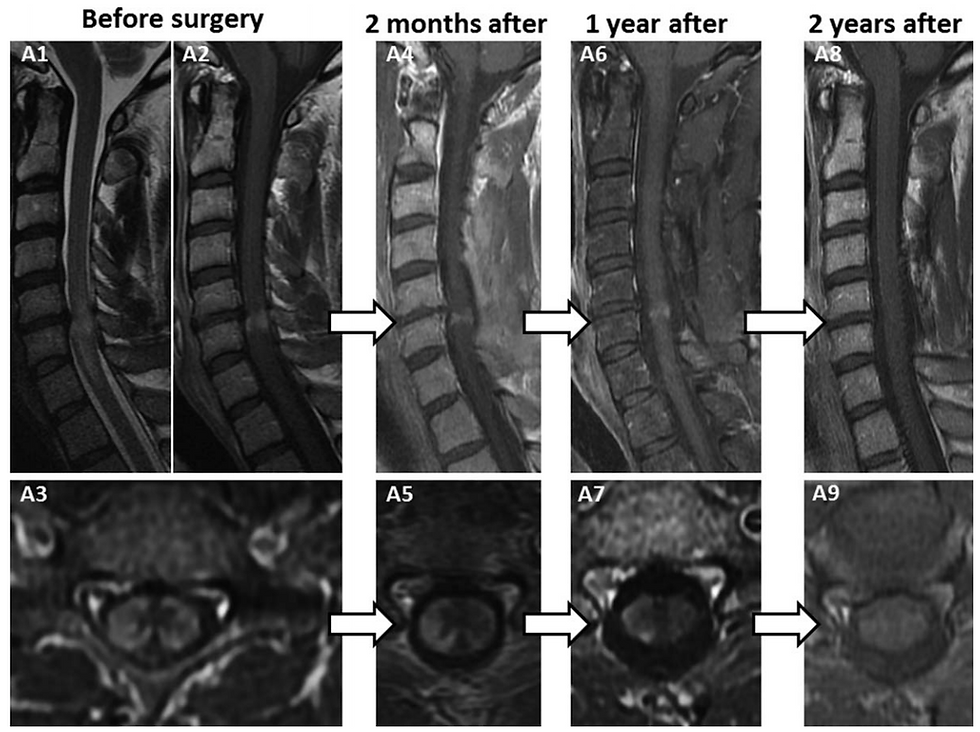

脊髄症では脊髄の異常信号域を呈しうるが、パンケーキ様と例えられる造影MRI異常所見は、術後臨床所見が改善しても残存・増悪しうると報告されている。

T2強調画像(矢状断)における紡錘状の高信号病変は100%,脊髄の腫脹は79%に認められた.パンケーキ・サインは73%に認められ,典型的には狭窄の一番強い部位のすぐ尾側に出現する.水平断では灰白質に造影所見が見られることはなく,脊髄の辺縁部分が造影される.

40例(71%)で,初期には腫瘍性ないし炎症性ミエロパチーと診断され,除圧術の施行は,中央値で11ヶ月(範囲1-64ヶ月)遅れた.白質のグリオーシスと血管周囲の炎症を認め,造影所見に関連する変化と考えられた.術後の経過では,95%の症例では,改善ないし症状の安定が見られた.

ガドリニウム造影所見は程度は軽減するものの,術後12ヶ月の時点で75%の症例で持続した.最終の診察時(中央値60ヶ月[10-172ヶ月])において, 20例(36%)が歩行時の介助を要したが,これを予見する因子として,術前における歩行の介助が挙げられたが,手術の遅れは関与しなかった.